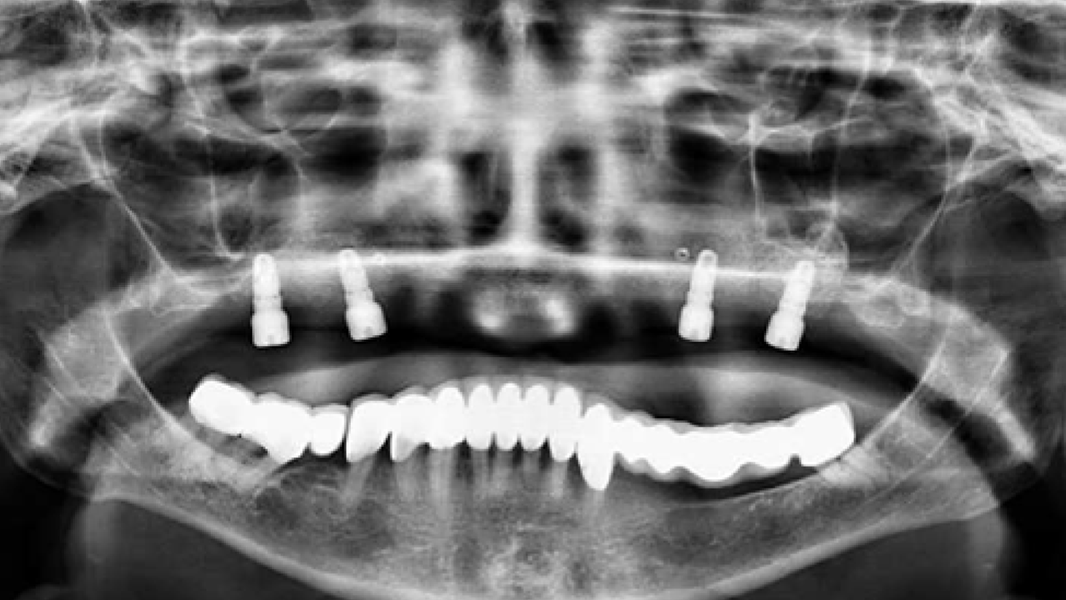

Die rein spongiösen Granulate ermöglichen durch eine zügige Remodellierung einen schnellen Knochenaufbau bei eingegrenzten Defekten, wohingegen das kortiko-spongiöse Material beim Aufbau ausgeprägter knöcherner Defekte für eine längere Volumenstabilität sorgt.

- In einer vergleichbaren klinischen Studie wurde bei Patienten, die mit MinerOss A behandelt wurden, eine signifikant höhere Knochenneubildung nachgewiesen als bei Patienten, die mit bovinem Knochenmineral behandelt wurden.8

- Die schnelle Remodellierung von MinerOss A verkürzt die Wiedereingliederungszeit und ermöglicht die Implantation nach 3–4 Monaten.9, 10

- Kein klinischer Unterschied in der endgültigen Integration im Vergleich zu autologem Knochen3, 5, 18